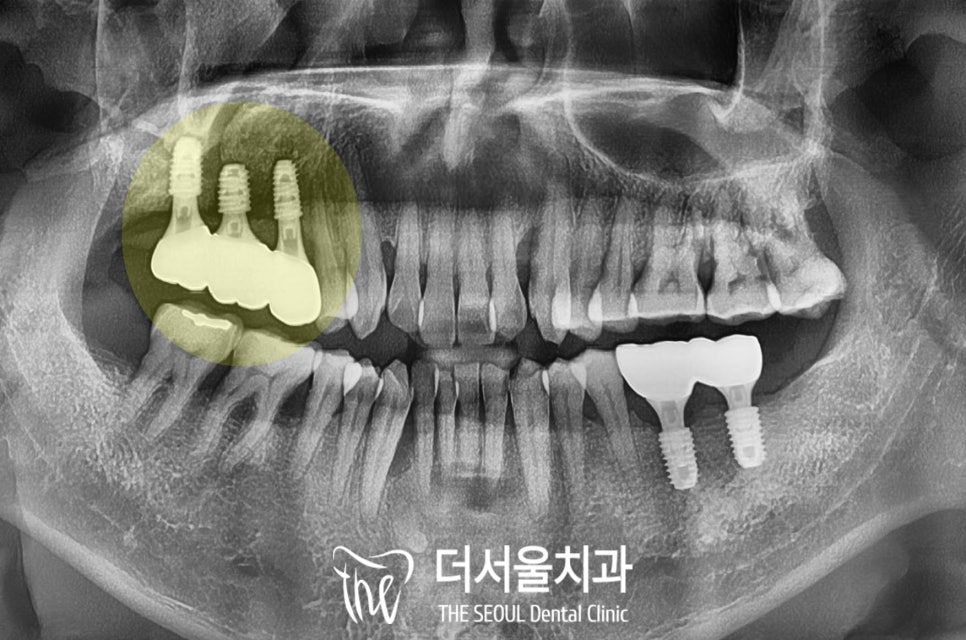

5. 식립 후 보철 수복

수진동 임플란트 식립 후

약 3개월 정도

치조골과 잇몸뼈가 단단하게 굳기를

기다리는 동안에는

흡연으로 인하여

회복에 방해가 되는 상황은 아닌지

꼼꼼하게 확인했기에

최종 보철까지 건강하게 잘 올라갔습니다.

상악동 하방으로

이식한 뼈들도 깨끗하게 잘 유착되고

잇몸도 예쁘게 아물었으며

브릿지 타입으로 제작 후

씌워드렸기에

강한 어금니 저작력에도

오래오래 버틸 수 있을 겁니다.